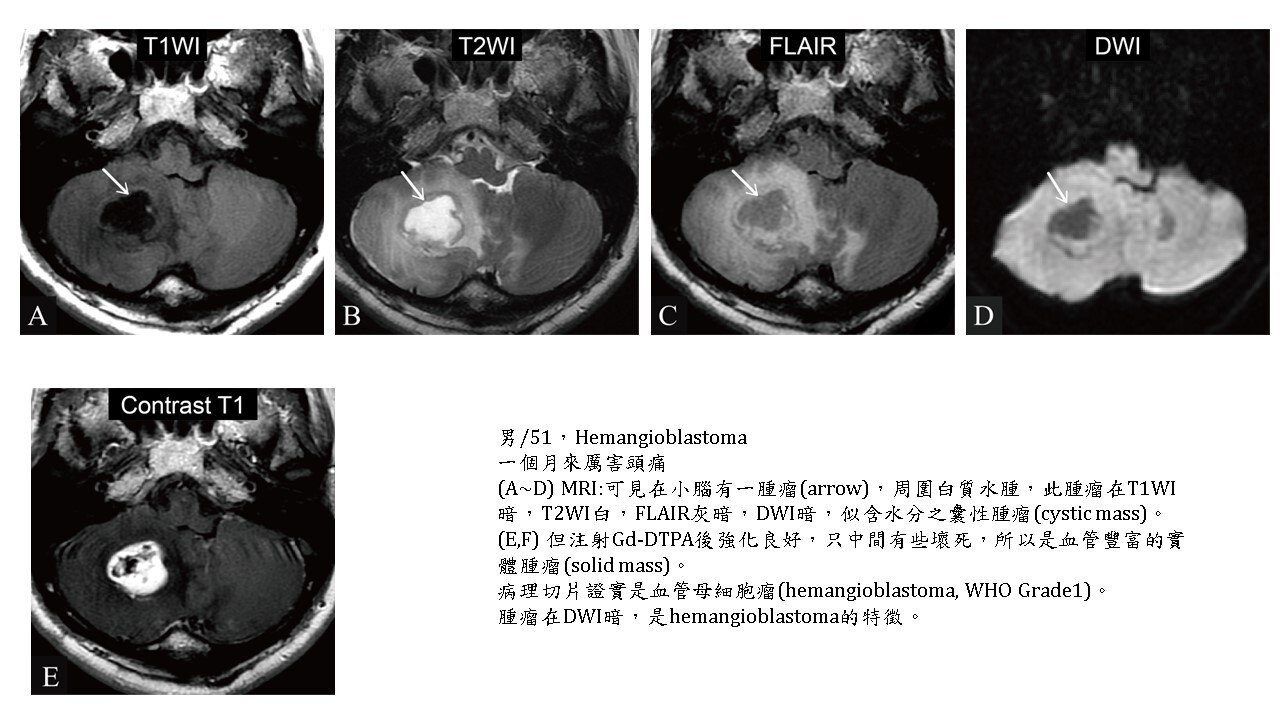

大多數的腫瘤(brain tumors)的實體部分(solid part),不管良性及惡性,DWI都會稍白,但對於血管豐富的hemangioblastoma, hemangiopericytoma則DWI暗。

腫瘤囊化(cystic change)或壞死(necrosis)部分,呈現類似CSF訊號,即在DWI暗,ADC白。